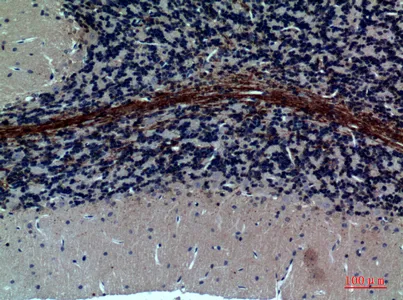

GABAA Rα1 Rabbit Polyclonal Antibody

Cat: APRab11233

Size1:50μl Price1:$118

Size2:100μl Price2:$220

Size3:500μl Price3:$980

Size2:100μl Price2:$220

Size3:500μl Price3:$980